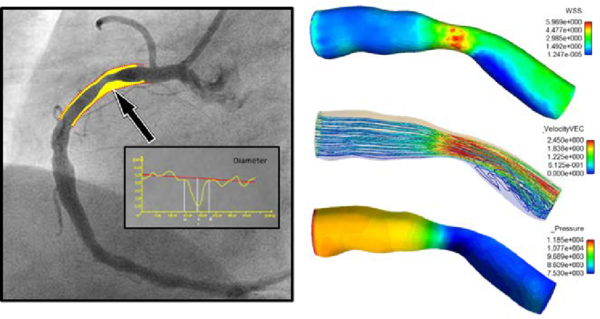

1.2.1.2 Coronary Artery Disease

Coronary artery disease(CAD) is the most common type of heart disease and cause of heart attacks. CAD is caused by abnormal narrowing of the coronary arteries (coronary stenosis) resulting in reduction of blood flow to the heart. The stenosis impedes to deliver oxygen to the heart muscle, which provoking heart attack. This disease is directly related with the atherosclerosis plaque. When stenosis occurs, the common clinical practice for decision taking related to the need (or not) of implanting a stent in a obstructed coronary artery requires the measurement of the Fractional Flow Reserve (FFR). FFR is derived from measuring the ratio of aortic pressure and pressure beyond a stenosis. Stenting is a specialized treatment for coronary arteries that are narrowed or blocked by plaques. It involves placing a balloon into the narrowed portion of the coronary artery with a surrounding wire mesh (stent). When the balloon is expanded, the stent remains in the vessel keeping the plaque pushed outwards, to let blood flow to the heart pass by.

|

| Figure 6: Streamline and wall shear stress in a coronary artery |

In recent years, several alternative methods based on Computational Fluid Dynamics (CFD) have been proposed for non-invasive estimation of coronary blood flow circulation [43]. CFD has been applied to coronary computed tomography angiography for computation of FFR. However, accuracy of method[44][45] and diagnostic accuracy remains suboptimal[46]. The main challenges for such methods are the lack of patient-specific data including anatomy, patient-specific boundary conditions, the condition of the microvasculature of the myocardium, and the large-scale computational resources required for the complex calculations. In [47] pressure gradients are computed using CFD in which the geometry of the aorta is extracted from MRA. Additional MR Phase contrast imaging is performed to measure the velocity which is used as boundary conditions. In [28] lumped parameter models of the heart, systemic circulation and coronary microcirculation are coupled to a patient specific 3D model of the aortic root and epicardial coronary arteries extracted from CTA. Disadvantages of these approaches are that all calculations are performed exclusively in 3D as well as the fact that the calculations cannot be performed during intervention because of the need for CT. Moreover, one vital piece of information is still missing in CFD, namely the condition of the coronary circulatory auto-regulation, also known as the patients cardiac flow reserve. This results in a method that is of high computational complexity. A recent study applied CFD to three dimensional X-ray angiography for the computation of the FFR incorporating the coronary flow reserve[48]. However, this method requires X-ray angiographic imaging during hyperemia which is a burden to the patient. Placing known side effects of adenosine into perspective; reduced blood flow to the heart which might worsen symptoms in patients with coronary heart diseases or even cause a heart attack, this is clearly an undesired situation especially during diagnostic coronary angiography.